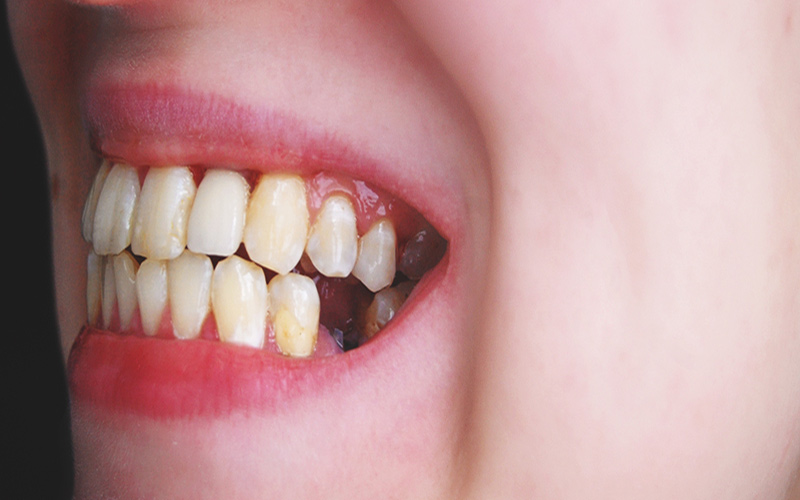

Răng hàm bị sâu dẫn đến vỡ chỉ còn lại chân răng là tình trạng mà nhiều người hiện nay đang mắc phải và nó cũng là nguyên nhân gây ra nhiều biến chứng, khiến sinh hoạt hàng ngày, sức khỏe răng miệng và sức khỏe toàn thân bị ảnh hưởng nặng nề đến.

Nếu sâu răng không được điều trị sẽ dẫn đến phá hủy nhiều hơn các tổ chức cứng của răng, từ đó làm cho răng dễ vỡ, mẻ và sau cùng chỉ còn sót lại chân răng. Lúc này răng cũng mất đi chức năng ăn nhai.

Răng hàm bị sâu vỡ chỉ còn chân răng ảnh hưởng đến chức năng ăn nhai